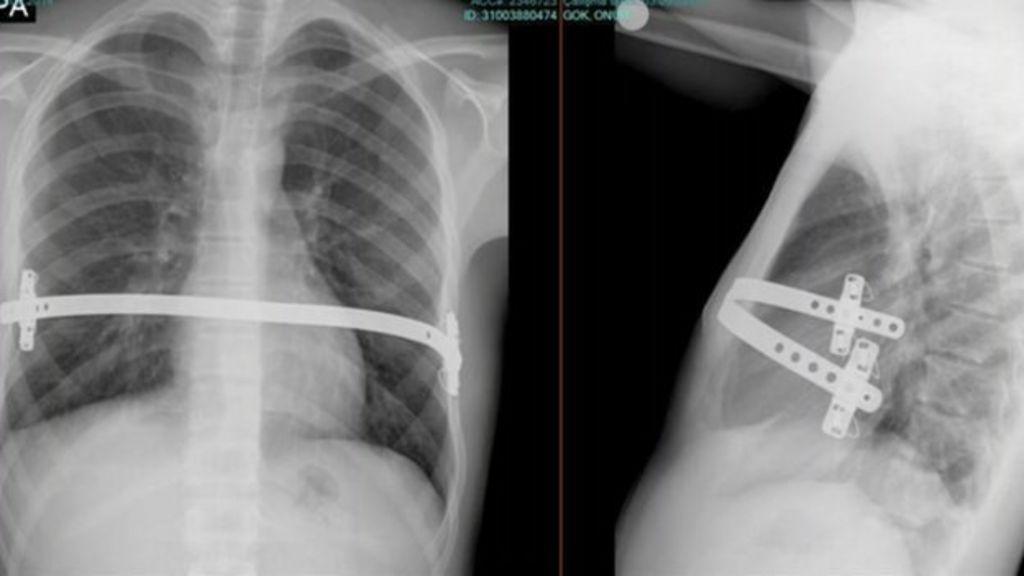

Pioneering chest deformity op carried out at Cardiff hospital BBC News What Is Chest Deformity Pectus excavatum (pe), translated literally as “hollowed chest” and also referred to as sunken chest or funnel chest, is the most common chest wall deformity seen in children. Pectus excavatum (funnel chest) and pectus carinatum. Pectus excavatum causes the breastbone to sink into the chest. Surgery helps correct the deformity. Pectus excavatum causes the breastbone to sink into the chest.. What Is Chest Deformity.

Pioneering chest deformity op carried out at Cardiff hospital BBC News What Is Chest Deformity Surgery helps correct the deformity. This can affect heart and lung function. Pectus excavatum causes the breastbone to sink into the chest. Home health conditions and diseases. Surgery helps correct the deformity. These can manifest as isolated conditions or can correlate. Pectus excavatum causes the breastbone to sink into the chest. A chest wall deformity is a structural abnormality of. What Is Chest Deformity.